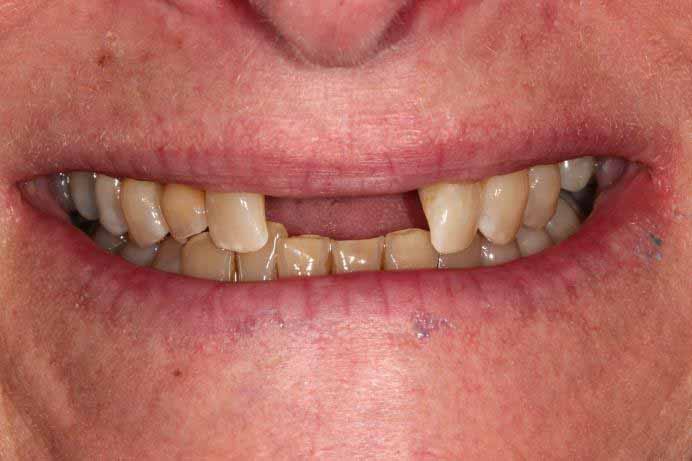

This patient had missing teeth and the those that remained were failing. After discussing with the patient, it was decided to remove the failing teeth and rehabilitate with same day all on 4 dental implants.

This treatment is usually carried out in 1 day (after a few preparatory appointments for moulds, x-rays, etc). The failing teeth were removed and implants place on the same day, with a temporary bridge (fixed teeth) attached also on the same day. Following a period of 3 to 6 months, moulds were taken and the definitive bridge placed